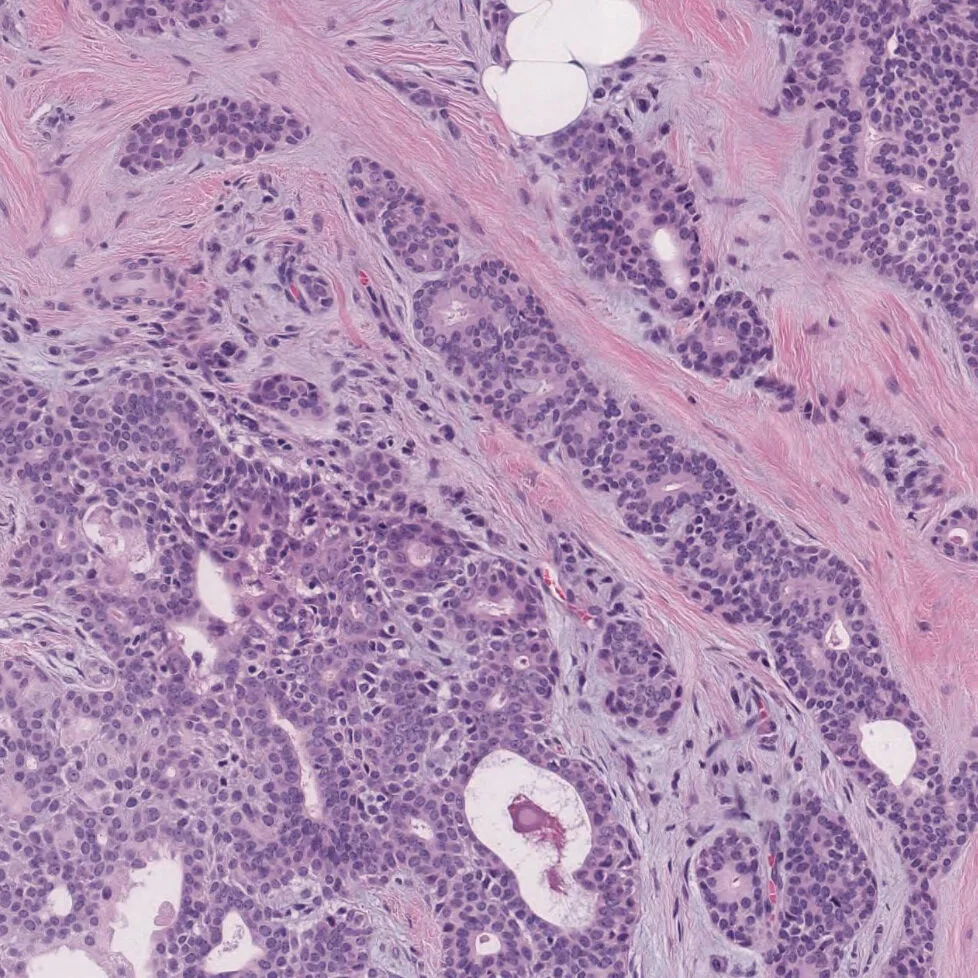

Head And Neck Pathology Journal - Anatomical area of the mouth, jaws, face, and skull, head. This article has been updated. Web head and neck pathology is a diverse field encompassing thyroid, parathyroid, salivary, the upper aerodigestive tract, odontogenic, sinonasal, and skull base regions. Web head and neck cancer (hnc) is a group of epithelial malignancies involving the upper shared respiratory/digestive tract (lips, oral cavity, oropharynx, nasal cavity,. Web archive of head and neck pathology. Update from the 4th edition of the world health organization classification of head and neck tumours: Tumors of the salivary gland. An author correction to this article was published on 19 january 2023. Web head & neck is an international otorhinolaryngology journal publishing original research concerning the diagnosis and management of diseases of the head and neck. Search all head and neck pathology articles.

Web head & neck is an international otorhinolaryngology journal publishing original research concerning the diagnosis and management of diseases of the head and neck. Web head and neck pathology is a hybrid journal that publishes research and reviews on pathology of the oral cavity, sinonasal tract, larynx, hypopharynx, salivary gland, ear,. Web head and neck cancer. Web head and neck cancer (hnc) is a group of epithelial malignancies involving the upper shared respiratory/digestive tract (lips, oral cavity, oropharynx, nasal cavity,.